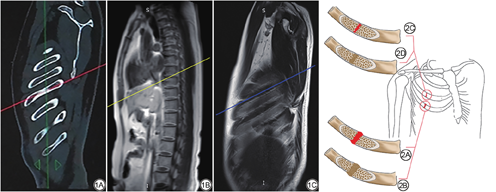

所有患者采用联影64排螺旋CT (United Imaging,中国)进行扫描。在扫描过程中,患者被要求抬起手臂,吸气后屏住呼吸。扫描范围从胸廓开口到第十二肋骨的下缘。扫描参数:管电压120 kV,螺距1.0875,阳极旋转时间0.5 s,扫描厚度5 mm,层间距5 mm。采用骨重建算法(窗宽1500 HU,窗位550 HU)进行薄层轴向重建,层厚1.0 mm,层间距0.8 mm。将薄层轴位图像发送到后处理工作站,在工作站上进行斜横断位重建,层厚和层间距均为3 mm,重建角度与肋骨长轴大致平行,尽可能将目标肋骨显示在同一层面上(图1A)。

所有患者使用飞利浦(Achieva,荷兰)或西门子(Magnetom Prisma,德国) 3.0 T MRI仪和8通道相控阵腹部线圈进行扫描。采用短时反转恢复序列(short time inversion recovery,STIR)及T2预饱和脂肪抑制序列(T2-weighted spectral adiabatic inversion recovery,T2-SPAIR),且均为斜横断位扫描(图1B、1C),扫描角度可参考CT重建角度。飞利浦MRI仪扫描参数如下:(1) STIR序列,重复时间(repetition time,TR)=2182 ms,回波时间(echo time,TE)=60 ms,图像视野(field of view,FOV)=35.0 cm×42.2 cm,层厚3.0 mm,层间距3.0 mm,平静呼吸扫描,时间5 min;(2) T2-SPAIR序列,TR=1100 ms,TE=70 ms,FOV=40.0 cm×35.6 cm,层厚3.0 mm,层间距3.0 mm,屏气扫描,分3次完成,共需45 s。西门子MRI仪扫描参数如下:(1) STIR序列,TR=2740 ms,TE=65 ms,FOV=40.0 cm×32.4 cm,层厚3.0 mm,层间距3.0 mm,平静呼吸扫描,时间5 min;(2) T2-SPAIR序列,TR=2530 ms,TE=73 ms, FOV=40.0 cm×30.0 cm,层厚3.0 mm,层间距3.0 mm,屏气扫描,分3次完成,共需45 s。首先用STIR序列从胸廓开口扫描至第12肋骨下缘,然后确定肋骨骨折的范围,最后根据确定的范围进行T2-SPAIR序列的扫描。若骨折范围大,T2-SPAIR序列可分两次进行扫描。一位患者可在10 min内扫描完成。

根据肋骨骨折的复查CT特征将细微肋骨骨折分为两型(图2),Ⅰ型为骨皮质完全或不完全断裂,伴有外生骨痂和/或骨内骨痂形成,Ⅱ型为骨皮质显示完整,伴有骨内骨痂形成,后者代表骨小梁发生了微骨折但未明显累及骨皮质。